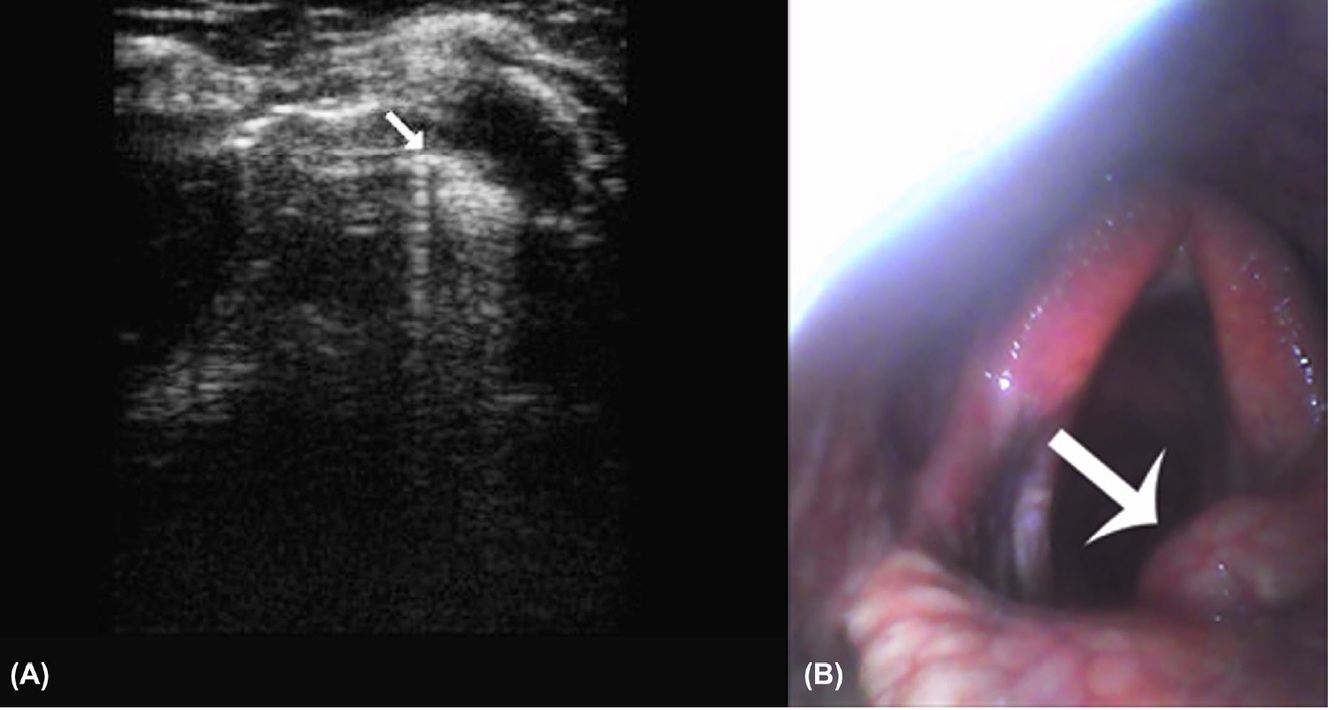

FIGURE 13 B, The corresponding right Plica vocalis at 30-50 days postsurgery on endoscopy. The Plica vocalis abscess clearly seen as a yellowish-greenish

mass covered in mucoid material (white arrow). Right to the left of the image

FIGURE 15 Caudoventral window – transverse plane: A, The left Plica vocalis at 6-12 months postsurgery. Plica vocalis base (white arrow) is

hyperechoic compared to the right Plica vocalis. This is consistent with thickening of the tissue in this area, attributed to a granuloma. There is a

luminal ringdown artifact created by this mass. Right to the left of image and the skin/ventral at the top. B, The corresponding right Plica vocalis at

6-12 months postsurgery on endoscopy. The Plica vocalis granuloma can be clearly seen (white arrow). Right to the left of the image [Color figure

can be viewed at wileyonlinelibrary.com]